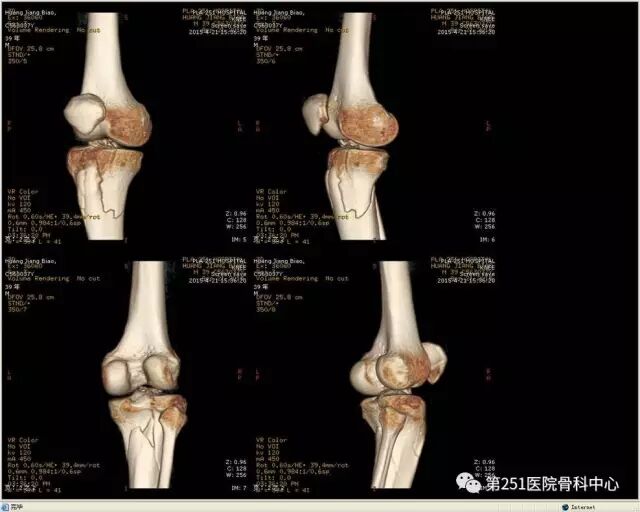

病例6:男性,39岁,车祸伤SchatzkerⅥ型胫骨平台骨折。

![]()